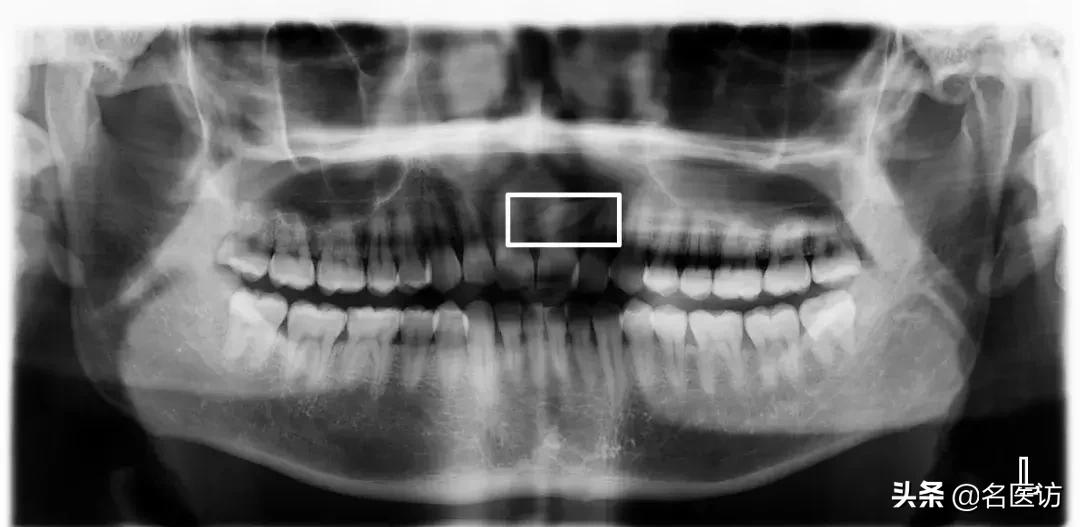

埋伏牙

多生牙